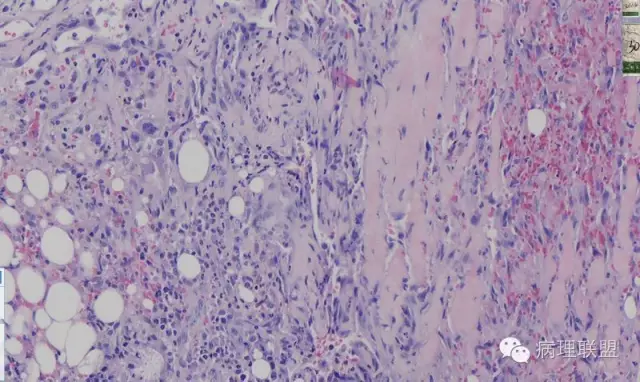

这例我们发的是卡波西样血管内皮细胞瘤,考虑如下:(1)新生儿,肢体肿物;(2)位置深,侵及皮下脂肪;(3)大多是裂隙状血管,也有少量吻合的血管网,细胞有异形,可见坏死

Kaposi型血管内皮瘤常有隐约小叶结构,梭形细胞束间有毛细血管,细胞核异型性和分裂活性一般不明显,常见梭形细胞束和圆形"肾小球样"实性细胞巢混合存在。

而复合性血管内皮瘤则是由良性、中间性和恶性的成份组成,也是浸润性生长,常常侵犯皮下脂肪组织,此例细胞形态由梭形细胞、卵圆形细胞及上皮样细胞组成,形态可见良性区域、中间性区域及高分化血管肉瘤或上皮样血管肉瘤区域,因此,似乎复合性血管内皮瘤更妥。此类肿瘤可以发生于婴幼儿。当然与Kaposi型血管内皮瘤一样,同属中间性血管瘤,只是后者,若肿瘤体积大,可出现Kasabach-Merritt综合征。

这种形态若在老年人头面部就是血管肉瘤,而在婴幼儿就降级了。